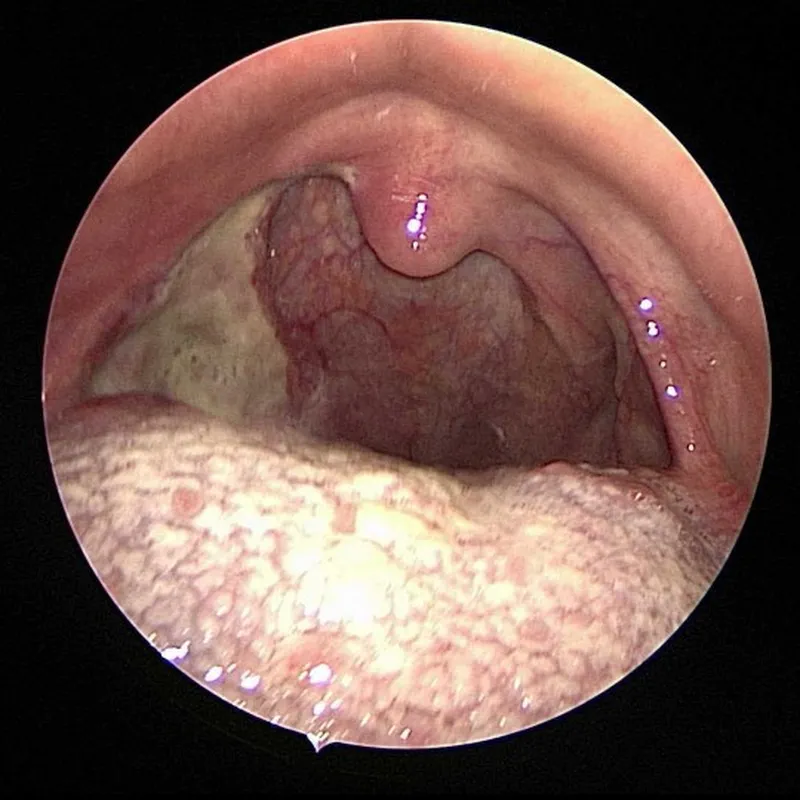

(땡큐서울의원에서

진단된 오른쪽 편도암

(인유두종바이러스HPV 양성)의 수술 전 및 수술 후 사진)